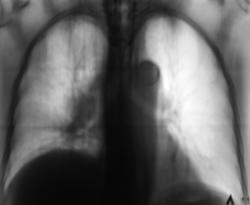

"боковые томограммы" правого лёгкого.

Спасибо коллеги за комментарии. Сегодня, добавлю "боковые томограммы" правого лёгкого.

В представленный случай добавлены боковые томограммы.

А мне что-то видится осумкованный экссудат в горизонтальной м/долевой щели, придавливающий сверху среднюю долю. Кажется есть и диафрагмальный экссудат. Обструкции крупного бронха не вижу, правда на этих томограммах не определяется Br2. Явная патология верхней доли без уменьшения её объёма. Бронхопульмональные лимфоузлы впечатляют, а вот медиастинальные что-то не очень. Ну допустим перибронхиальный рост…, но вдоль каких бронхов?